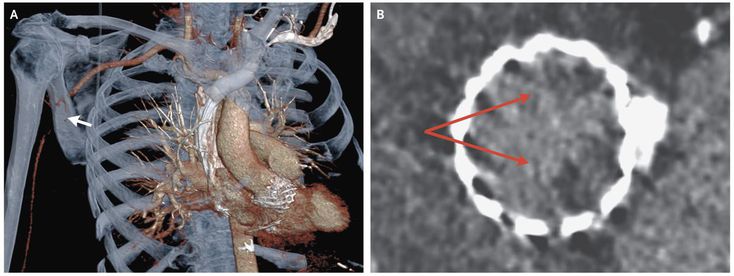

An 84-year-old man had sudden onset of severe pain and weakness in the right arm 7 days after undergoing transcatheter aortic-valve replacement (TAVR) for symptomatic aortic stenosis. Physical examination showed a pale right forearm, nonpalpable right radial and brachial pulses, and reduced strength in the right arm. Three-dimensional computed tomographic angiography revealed an occlusion of the right axillary artery (Panel A, arrow), and a two-dimensional angiogram showed hypoattenuated thickening of the noncoronary and left coronary aortic leaflets (Panel B, arrows). Surgical thrombectomy was performed, and a fresh thrombus was removed. Transesophageal echocardiography that was performed after thrombectomy revealed a thickened noncoronary aortic leaflet but no intracardiac thrombus. The transvalvular gradient was measured at 15 mm Hg, an increase from 8 mm Hg measured after TAVR. After thrombectomy, the pain and weakness in the patient’s right arm resolved. Aspirin and clopidogrel, which had been the dual antiplatelet therapy initiated after TAVR, were discontinued, and treatment with an oral anticoagulant was initiated.